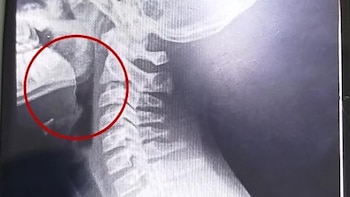

A continuación, se desarrollaron distintos estudios para descartar la presencia de infecciones o bacterias, cuyos resultados resultaron negativos. La clave para entender el cuadro apareció tras la realización de estudios por imágenes: las placas evidenciaron la presencia de un objeto extraño alojado en la vía aérea superior.

El parte médico consignó que el paciente ingresó “clínica y hemodinámicamente estable, afebril, vigil, reactivo, normohidratado y normoperfundido”, según el medio local. Luego de una interconsulta con el servicio de otorrinolaringología, se resolvió su ingreso urgente a quirófano. Allí, el equipo médico halló un alambre fino incrustado en la garganta del adolescente, situación que no había sido advertida previamente.